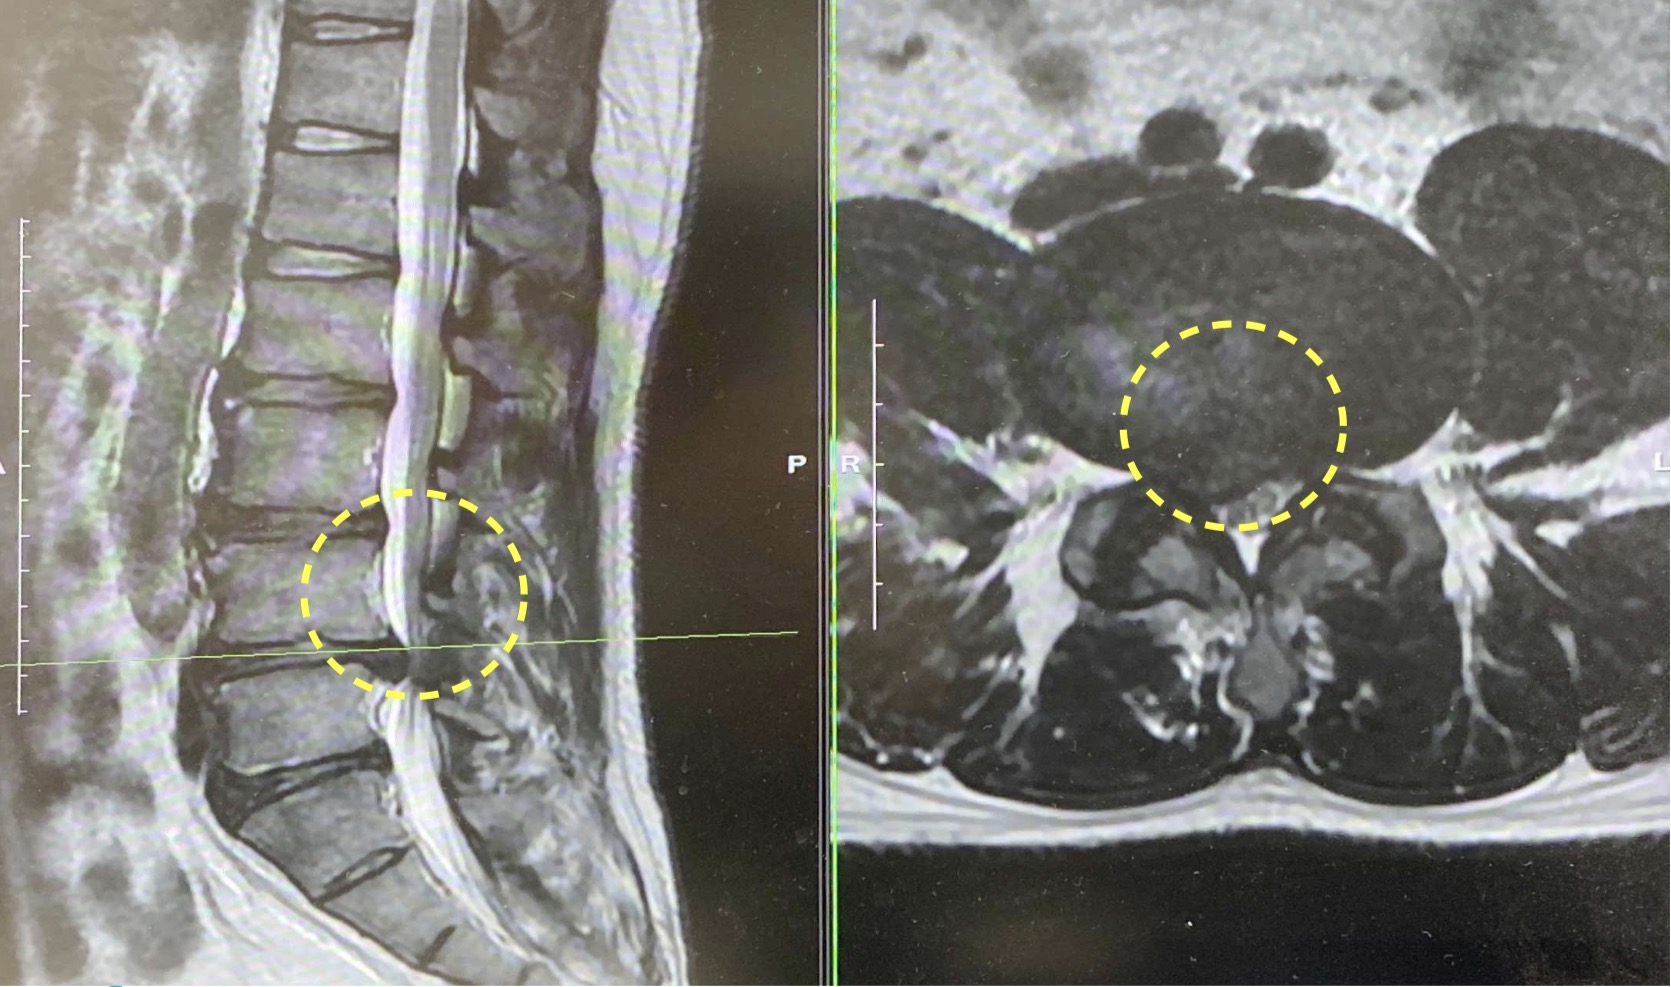

診察および画像検査の結果、腰椎椎間板ヘルニアと診断されました。椎間板ヘルニアとは、背骨のクッションの役割を果たす椎間板が飛び出し、近くの神経を圧迫することで腰痛や下肢の痛み・しびれを引き起こす疾患です。

本症例では、保存療法(投薬やリハビリ)を経ずに来院された段階で、すでに日常生活や仕事への影響が大きく、歩行困難も伴っていたことから、内視鏡下椎間板摘出術(MED)による外科的治療の方針となりました。MED(Microendoscopic Discectomy)は、小さな切開から内視鏡を挿入して行う低侵襲手術であり、身体への負担が少なく早期回復が期待できる術式です。